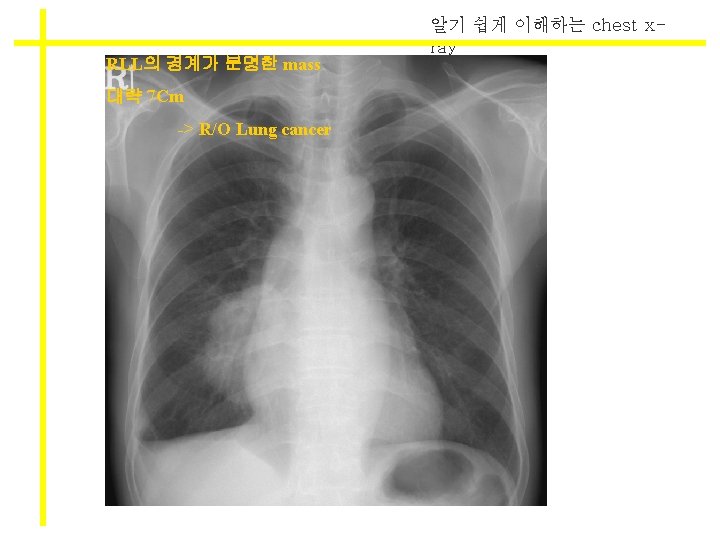

알기 쉽게 이해하는 chest xray density(음영)의 이해 * Density의 증가? * l White l Infiltration / hazziness l consolidation l GGO (ground glass opacity) l Cavity l Pneumonia, pulmonary edema, pleural effusion

알기 쉽게 이해하는 chest xray * density의 감소 * l Black l lucent l pneumothorax , emphysema